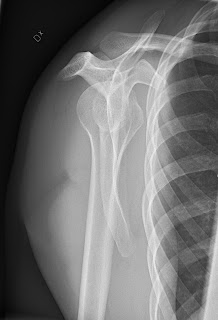

X-Ray of Shoulder